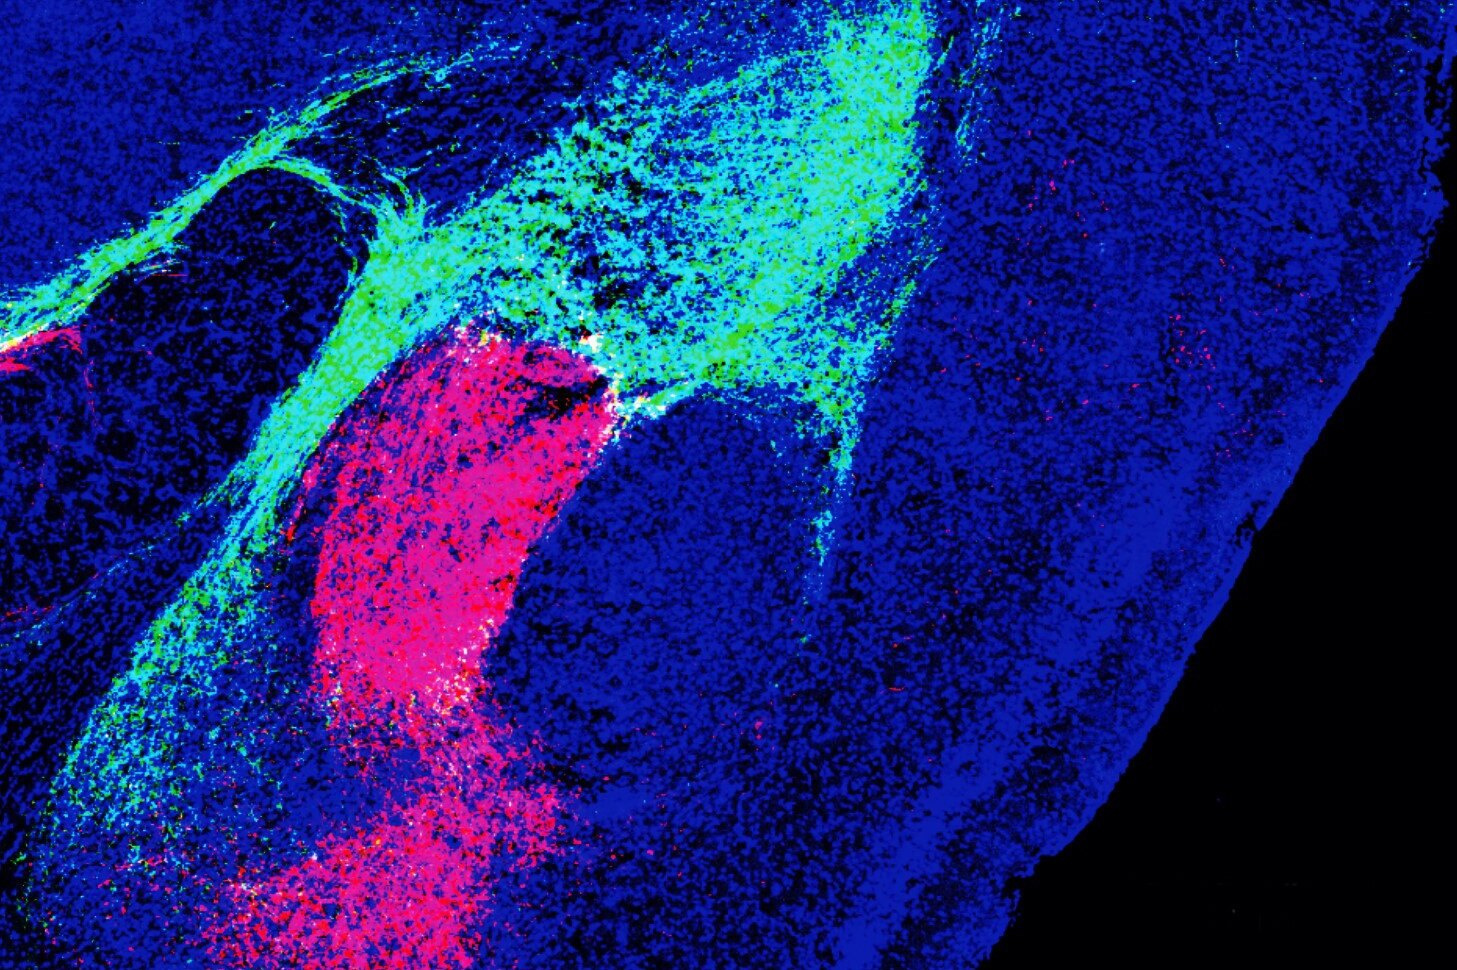

Ученые из Института Солка обнаружили молекулярный путь, который объединяет угрожающие образы, звуки и запахи в одно сообщение: «Бояться!». Молекула под названием CGRP позволяет нейронам двух разных областей мозга объединять угрожающие сенсорные сигналы в один, помечать его как негативный и передавать в миндалевидное тело, которое "включает" чувство страха. Это важный шаг в лечении многих нервных расстройств, в том числе аутизма.

Исследование, опубликованное учеными из Института Солка, может привести к новым методам лечения расстройств, связанных со страхом, таких как посттравматическое стрессовое расстройство (ПТСР) или расстройства гиперчувствительности, такие как аутизм, мигрень и фибромиалгия (хроническая мышечная боль).

Большинство внешних угроз связаны с мультисенсорными сигналами, такими как жар, дым и запах горящего дерева.

Предыдущие исследования показали, что различные нейронные пути независимо передают звуковые, визуальные и сенсорные сигналы угрозы в несколько областей мозга. Единственный суммарный сигнал, объединяющий все эти частные сообщения, был бы полезен для выживания, поскольку реакция на него является быстрой и однозначной. Но до сих пор понять, как формируется такой сигнал,